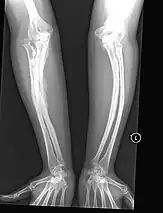

The main symptom of osteogenesis imperfecta is fragile, low mineral density bones; all types of OI have some bone involvement.[5] In moderate and especially severe OI, the long bones may be bowed, sometimes extremely so.[28] The weakness of the bones causes them to fracture easily; a study in Pakistan found an average of 5.8 fractures per year in untreated children.[29] Fractures typically occur much less after puberty, but begin to increase again in women after menopause and in men between the ages of 60 and 80.[1]: 486

Diagnosis is typically based on medical imaging, including plain X-rays, and symptoms. In severe OI, signs on medical imaging include abnormalities in all extremities and in the spine.[97] As X-rays are often insensitive to the comparatively smaller bone density loss associated with type I OI, DEXA scans may be needed.[5]: 1514